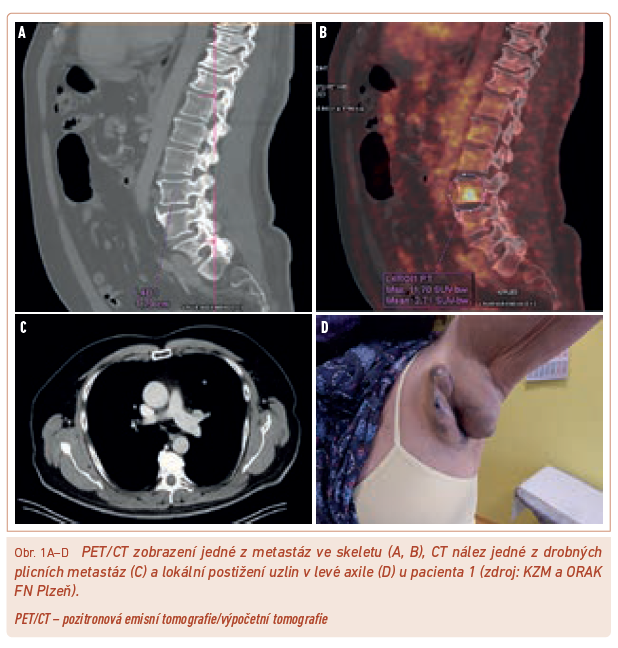

S ohledem na schopnost nádoru poměrně časně diseminovat je však zejména u pokročilejších lézí nutno doplnit další vyšetření, která pomohou určit stadium onemocnění. Nemocní by měli mít doplněno alespoň rentgenové (RTG) vyšetření plic a sonografické (SONO) vyšetření spádových uzlin a epigastria. Jelikož je dnešní léčba pokročilého a metastatického melanomu nákladná, jsou upřednostňována komplexnější a přesnější vyšetření – spíše výpočetní tomografie (CT) hrudníku a břicha nebo nejlépe vyšetření celotělovým PET/CT (pozitronová emisní tomografie/výpočetní tomografie) (obr. 1) umožňující posoudit i nález ve skeletu a mozku, který by měl být před zahájením terapie rovněž vyšetřen, aby byla možná úhrada léčby ze zdravotního pojištění. Navíc je CT nález přesnější a přehlednější, než jaký umožní běžné SONO vyšetření (obr. 2).